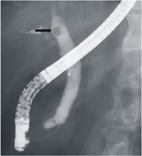

有經驗的醫師藉由以上的臨床表現,即可初步的診斷出病患目前的問題,然後再藉由下列檢驗及工具做進一步的確定診斷。診斷方法與工具,可藉由(1) 血液檢驗,白血球增生、血清轉氨脢 (GOT/GPT)和鹼性磷酸脢升高,甚至膽紅素或澱粉脢上升。(2) 腹部超音波檢查,常用來偵測肝膽管結石的第一線診斷工具,因為它方便且非侵襲性;當肝膽管因結石出現膽汁滯留時,膽管會出現擴張,膽囊飽脹,甚至直視到結石位置及大小。(3) 電腦斷層攝影:在西方國家,最常用來了解肝膽管構造和結石性質,主要著眼於西方病人體型肥胖,腹部超音波檢查於診斷上較受限制;但電腦斷層檢查的技術與設備層面複雜性高,有方便性不足和費用高的缺點,而且結石太小,往往易有診斷上誤差。(4) 核磁共振膽胰管造影(MRCP):目前已漸被接受為另一種不具侵犯性的檢查,而可以清楚顯示膽胰管之解剖構造,但無法做治療性處置是其缺憾。(5) 內視鏡逆行性膽胰管造影(ERCP):這是目前最常使用的診斷方法,乃藉由十二指腸鏡導引至十二指腸乳頭(膽胰管開口),再經內置導管放入膽、胰管內,並施打顯影劑來顯現結石(圖一)或阻塞的位置和病因。

內視鏡逆行性膽胰管造影術(ERCP): 打完顯影劑顯後現出結石的位置(箭頭處)。

內視鏡逆行性膽胰管造影(ERCP)有分成兩種:診斷性ERCP是利用十二指腸鏡將一支細導管插入膽管或胰管,然後注射顯影劑以觀察膽管或胰管的構造。治療性ERCP是利用十二指腸鏡放入一些治療用的小器械,以處理膽管或胰管內的病變。包括放入引流管及支架、碎石與取石、狹窄擴張術等。這些治療措施是在完成膽胰管造影術後並以內視鏡以電刀切開十二指腸乳頭後,再把結石取出(圖二)或者置放引流管。這類治療措施,目前被認為是相當有效且安全的非開刀之治療方式,然而也有一定的風險包括: (1) 對藥物或顯影劑之不良反應 < 0.2% ;(2) 出血 2-9 % ;(3) 膽管炎 0.5-1.3 %; (4) 胰臟炎 1-18 % ;(5) 穿孔 1%; (6) 吸入性肺炎及心肺系統併發症 < 1%。支架放置術併發症: (1) 膽囊炎 0-14 %;(2) 膽管炎 7-27 % ;(3) 阻塞 1-2 % ;(4) 穿孔 1-2 % ;(5) 胰臟炎 1-18 % 。其餘罕見之併發症有取石器嵌塞、導線脫落、肝膿瘍、囊腫感染等。

膽胰管造影術後並以內視鏡以電刀切開十二指腸乳頭後,再把約1.5公分結石取出。